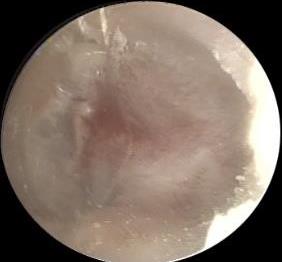

• 耳内镜下耳屏软骨-软骨膜鼓膜修补术后的短期疗效观察

2025, 31(6):1-8. DOI: 10.12235/E20240626

摘要 (319) HTML (229) PDF 4.57 M (181) 评论 (0) 收藏

摘要:目的 探讨耳内镜下耳屏软骨-软骨膜鼓膜修补术后的短期疗效。方法 回顾性分析2019年9月-2022年8月该院收治的78例鼓膜穿孔患者的临床资料,患者均采用耳内镜下鼓膜修补术。术后随访3个月,观察鼓膜形态和穿孔愈合情况,记录内镜图像、干耳时间、术前术后听力及耳鸣情况,以及外耳道狭窄等并发症的发生率。结果 术后3个月,鼓膜穿孔愈合率为97.44%(76/78),愈合良好,平均气导听阈较术前明显改善,气骨导间距较术前明显缩小,耳鸣较术前明显改善,差异均有统计学意义(P<0.05)。干耳时间为(4.21±1.12)周。术后出现肉芽5例,再穿孔2例,真菌感染2例,术腔感染、耳屏感染、外耳道狭窄和切口瘢痕各1例,所有患者术后均未发生面神经麻痹和感音神经性聋等严重并发症。结论 耳内镜下耳屏软骨-软骨膜鼓膜修补术是一种安全、有效的手术方法。根据术后愈合规律、内镜下鼓膜和外耳道形态特征,可为鼓膜修补术后正常中耳转归和并发症的诊疗,提供临床参考。